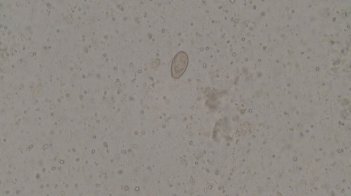

在医生的建议下,小凯一家三口都做了寄生虫相关检查,结果显示,三人血常规中嗜酸性粒细胞都异常升高!小凯还有肝功能异常,彩超显示肝内有片状低回声区,肝门淋巴结肿,妈妈的大便中检出肝吸虫卵!